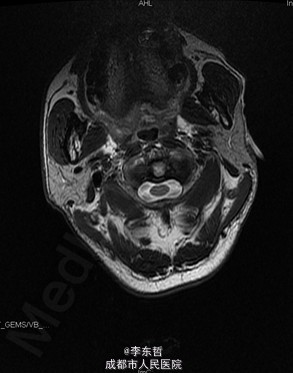

陈旧性寰枢关节脱位

患者男性,54岁,因“外伤后头颈部疼痛2年加重伴活动受限1个月”入院,自诉疼痛呈慢性起病,间歇性、反复发作并逐渐加重,为求进一步诊治故来我院,门诊以“陈旧性寰枢关节脱位”收入我科。